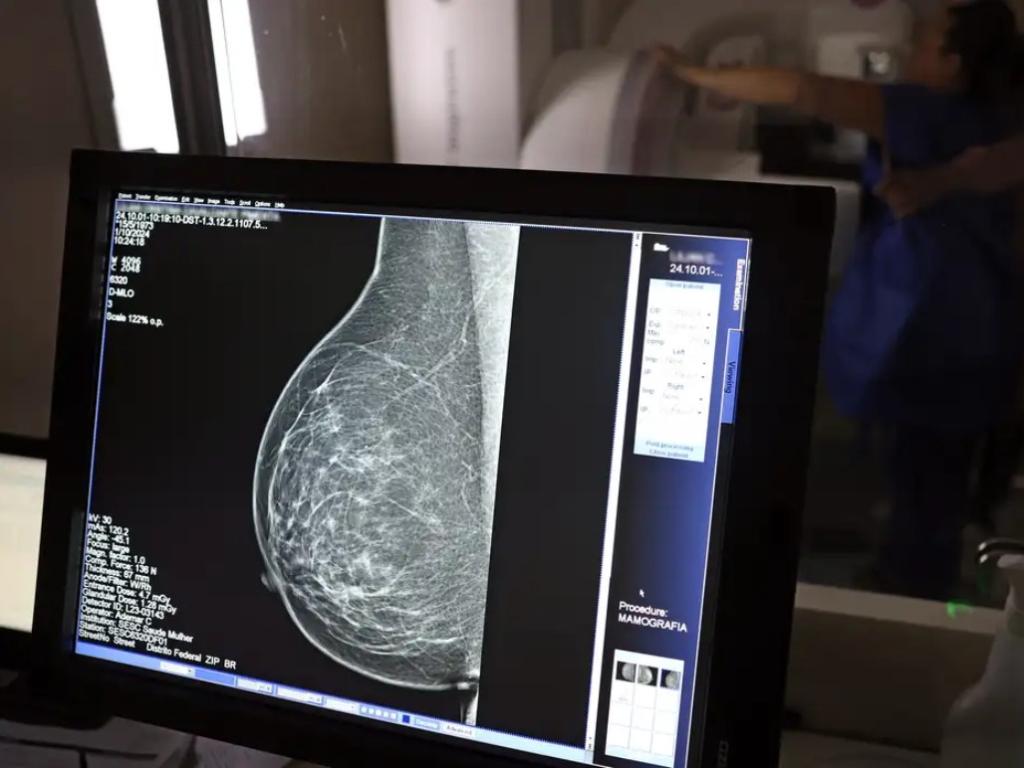

O direito já estava incluído na CLT desde 2018. A partir de agora, as empresas passam a ser obrigadas a divulgar essa informação, além de outras relacionadas a campanhas oficiais de vacinação contra o HPV e sobre o acesso a serviços de diagnósticos de cânceres de mama, próstata e de colo do útero.

O texto estende o uso das folgas também para a realização de exames preventivos do HPV, além dos de câncer que já estavam previstos na legislação anterior. A a Lei 15.377 foi sancionada pelo presidente Luiz Inácio Lula da Silva, e publicada na edição do Diário Oficial da União (DOU).